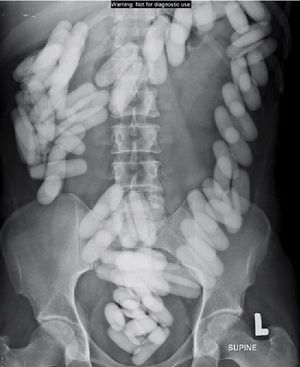

Body packing!!! It’s time for a bizarre foreign body case! “Body packing” refers to the “art” of internally concealing drugs within the gastrointestinal tract. They do this by either swallowing and/or inserting the drugs rectally, one at a time. This particular patient was arrested at an international airport for suspected drug smuggling. An X-ray was completed and confirmed the law enforcement’s suspicion via a positive “Tic-Tac Sign.” The patient evacuated a total of 84 intact packets of cocaine over the next 3 days! So what did we learn today? Don’t do drugs....or pack them in your colon🚫 By the Japanese Journal of Radiology - Suzana Ab Hamid, et. al. 2012 Credit to @drcellini